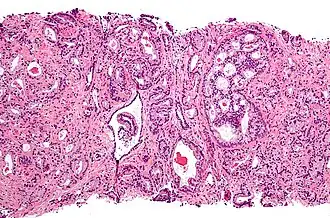

Histologie

Le diagnostic est obtenu par des biopsies prostatiques multiples, réalisées de manière échoguidée et par voie transrectale. Elle permet également de réaliser le score de Gleason, de grande valeur pronostique.

Anatomopathologie

Le cancer entreprend la portion périphérique de la glande, au contraire de l'hypertrophie prostatique bénigne qui intéresse la zone centrale, périurétrale.

La gravité de l'évolution est corrélée avec l'aspect microscopique (score de Gleason), le niveau de PSA et l'extension de la maladie[53].

Score de Gleason

La structure tissulaire des cancers de la prostate varie des formes différenciées (cellules cancéreuses ressemblant aux cellules saines), dite de grade 1, aux formes les moins différenciées (cellules cancéreuses présentant beaucoup de caractères atypiques par rapport aux cellules saines), dite de grade 5.

Plusieurs grades peuvent se rencontrer au sein d'un même tissu. Le score de Gleason est calculé de la façon suivante : on additionne les deux grades les plus représentés de la tumeur. Le premier chiffre représentant le score du contingent le plus représenté. Ainsi 4+3 est plus péjoratif que 3+4

Si la somme est de 6 ou moins, le cancer est dit bien différencié, donc de meilleur pronostic ; 7 : le cancer est moyennement différencié ; 8 ou plus : le cancer est peu différencié, donc de moins bon pronostic.

Aux stades T1 ou T2, N0, M0, le score de Gleason est bien corrélé à la probabilité de survie sans traitement[54].